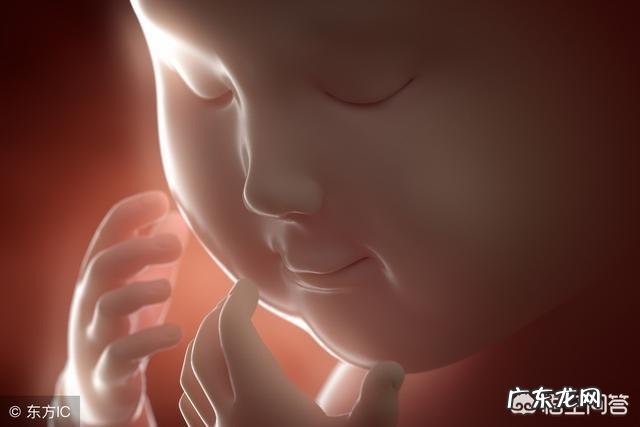

孕六个月的胎儿,皮肤薄薄的,皱巴巴的,像个小老头,五官清晰可见,但是距离我们习惯的样貌,还是有些差距的 。此时的胎儿,处于羊水的包围中,皮肤上面有一层皮脂保护着宝宝的皮肤,让原本就不太美的宝宝显得更加奇怪 。

由于宝宝发育还不太完善,样子本身就有些怪,加上四维仪器本就有些偏差,在羊水的作用下,你观察到的胎宝宝就是一个样子很丑的小老头:塌鼻梁或者朝天鼻,四肢奇怪的弯曲着,跟想象中的可爱宝宝差别不要太大,甚至会觉得自己怀了个外星宝宝 。

这些都是正常现象,胎宝宝在妈妈肚子里由于种种原因样貌显得很奇怪,但是,经过一两个月,宝宝慢慢成长发育,还会出现脱皮现象 。等到新的皮肤长成,丑小鸭就会长成粉嫩嫩肉嘟嘟的小胖鹅了 。妈妈只需要给宝宝提供足够的母乳和关爱就行啦 。